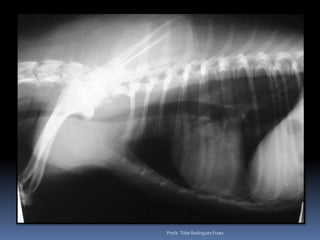

Animal: Dusty, felino, macho, 18 anos, SRDPesquisa de metastasesProfa. Tilde Rodrigues Froes

Animal: Dusty, felino,macho, 18 anos, SRDPesquisa de metastasesProfa. Tilde Rodrigues Froes